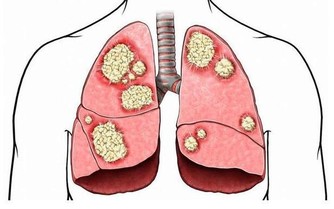

喝酒傷肝是大家都知道的道理,但如果你認為這裡說的傷肝是脂肪肝就大錯特錯了。酒精的成分是乙醇,乙醇需要靠肝臟進行代謝,而肝臟有許多工作要做,分解酒精只是他其中一項任務,所以每次都只能負荷一定含量的酒精,如果持續飲酒過量,不管是一次喝或是每天持續喝,都會讓肝臟持續超量工作,形成脂肪肝或是酒精性肝炎、肝硬化,甚至肝癌。

有相關研究發現,每日飲白酒80-150克,連續5年即可造成肝損傷;大量飲白酒在20年以上,40%-50%的人會發生肝硬化;每日飲白酒200克延續10年可出現脂肪肝。

那麼對於肝功能已經出現問題的患者,戒酒後,肝臟可以自我修復嗎?英國有醫院研究發現,戒酒後身體的恢復可以說“立竿見影”。戒酒一個月,就能促進受損肝臟的恢復,還能降低血壓和膽固醇水平,罹患癌症和糖尿病的風險也會降低。戒酒一個月後,由於常年喝酒所導致的肝部損傷開始自我修復,肝硬化程度減輕了12.5%。同時,胰島素抵抗下降了28%,體重減輕、血壓降低,注意力和睡眠質量都會有所改善。